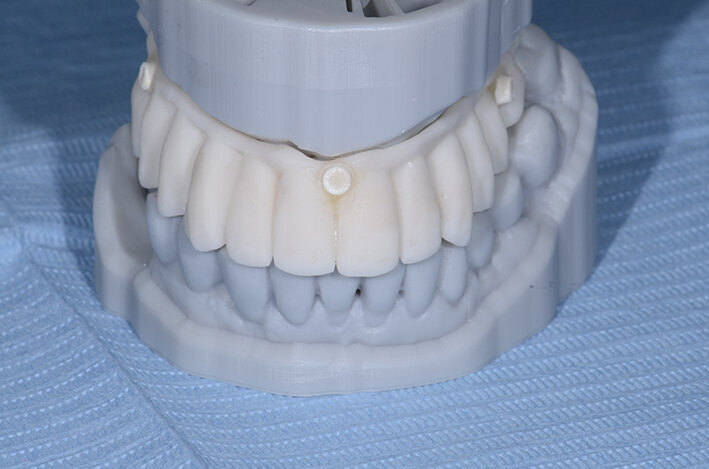

Inoltre da questa nuova ceratura dobbiamo ricavare una protesi radiografica con i punti di repere radiopachi che ci servirà per fare il matching con i nuovi file DICOM dell’osso rigenerato (Figg. 35, 36). Fatte le opportune verifiche nel software di chirurgia guidata, si pianifica l’intervento di posizionamento implantare (Figg. 37-40). Si programma lo stesso giorno della chirurgia anche il carico immediato degli impianti; decisione supportata dalla verifica istologica dell’osso rigenerato che dovrà comunque essere confermata il giorno del posizionamento implantare durante il quale si misurerà il torque di inserimento degli impianti e la stabilità primaria con il sistema OSSTELL mentor (Integration Diagnostics) che sfrutta l’analisi della frequenza di risonanza.

Grazie al flusso digitale, possiamo inserie nel software anche il file STL del provvisorio pre-chirurgico preparato e quindi progettare il provvisorio immediato (Fig. 41). La pianificazione degli impianti a questo punto viene effettuata in modo protesicamente guidato ed è facile posizionare correttamente l’impianto e verificarlo nelle cross del software. Si progetta e si disegna quindi la dima chirurgica (Fig. 42). Il giorno dell’intervento abbiamo già tutto pronto e la paziente presenta uno stato di salute dei tessuti ottimale grazie anche al fatto che ha potuto portare per tutto il periodo una protesi fissa.

Procediamo quindi all’inserimento di sei impianti BLX Straumann (Straumann Group) (Fig. 43, 44), ed utilizziamo gli impianti posizionati nella tuberosità per stabilizzare la dima chirurgica e il provvisorio sul modello master di lavoro digitale. La funzionalizzazione del provvisorio immediato subito dopo l’intervento viene effettuata con l’utilizzo della tecnica DIL19 (Figg. 45, 46).